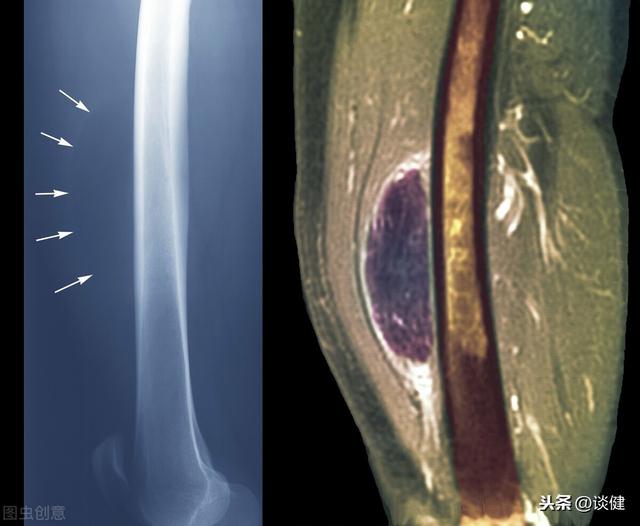

Si cela se produit.La grande majorité d'entre eux sont des lipomes.Toutefois, il ne s'agit que d'un simple diagnostic par palpation et inspection visuelle, et le diagnostic spécifique doit être combiné avec les résultats de l'examen clinique et l'analyse des antécédents médicaux du patient afin de porter un jugement correct. Par exemple, l'échographie couleur peut être utilisée pour déterminer la limite de la masse, la membrane dorsale, et pour observer les vaisseaux sanguins et les nerfs autour de la masse.

Lipome à l'échographie couleur

Bien que les lipomes soient des tumeurs bénignes, nous devons déterminer s'ils sont causés par d'autres tumeurs malignes présentant les mêmes modifications.Si la masse est entourée d'une réserve de sang, accumulant des nerfs et des vaisseaux sanguins importants, il faut craindre qu'il s'agisse d'une tumeur maligne. L'inspection visuelle, la palpation, l'observation par ultrasons et même l'analyse histopathologique de la composition de la tumeur nous permettront de poser un diagnostic définitif.En effet, même dans le cas de maladies bénignes, il convient d'être très rigoureux et de ne pas tirer de conclusions hâtives, faute de quoi le risque d'erreur de diagnostic est élevé, ce qui peut être un fléau pour notre santé.